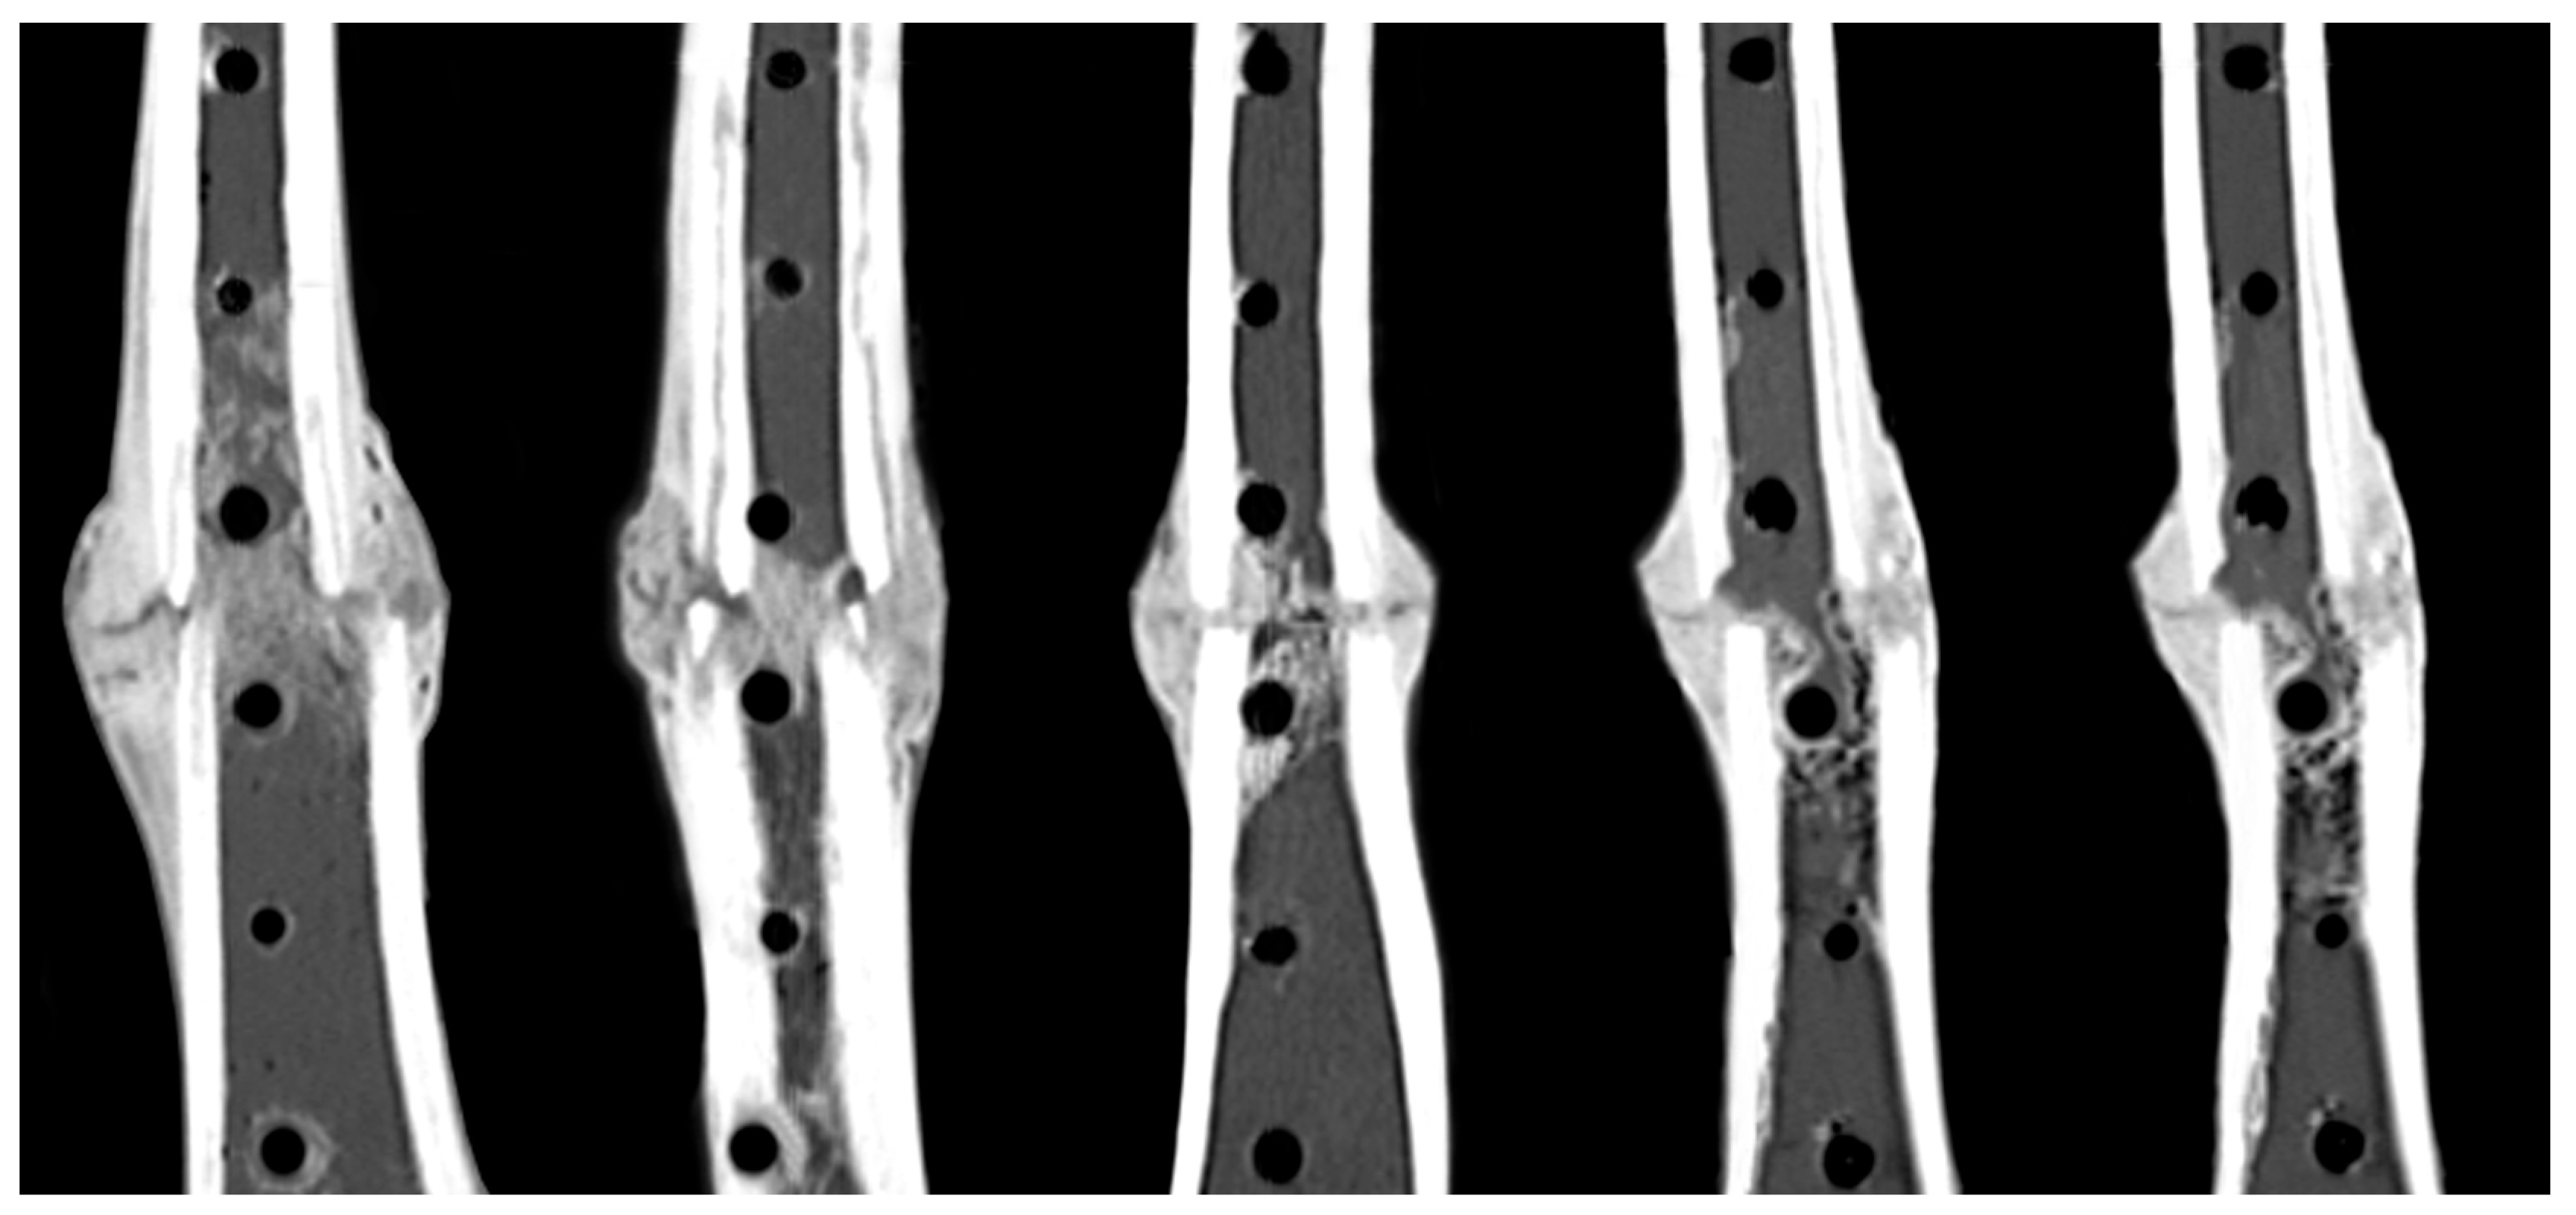

3.2. Healing Assessment

- Bottlang, M.; Tsai, S.; Bliven, E.K.; von Rechenberg, B.; Klein, K.; Augat, P.; Henschel, J.; Fitzpatrick, D.C.; Madey, S.M. Dynamic Stabilization with Active Locking Plates Delivers Faster, Stronger, and More Symmetric Fracture-Healing. J. Bone Jt. Surg. Am. Vol. 2016, 98, 466–474. [Google Scholar] [CrossRef] [PubMed]

- Bottlang, M.; Tsai, S.; Bliven, E.K.; von Rechenberg, B.; Kindt, P.; Augat, P.; Henschel, J.; Fitzpatrick, D.C.; Madey, S.M. Dynamic Stabilization of Simple Fractures With Active Plates Delivers Stronger Healing Than Conventional Compression Plating. J. Orthop. Trauma 2017, 31, 71–77. [Google Scholar] [CrossRef] [PubMed]

- Hofmann-Fliri, L.; Epari, D.R.; Schwyn, R.; Zeiter, S.; Windolf, M. Biphasic Plating—In vivo study of a novel fixation concept to enhance mechanobiological fracture healing. Injury 2020, 51, 1751–1758. [Google Scholar] [CrossRef] [PubMed]

- Han, Z.; Wu, J.; Deng, G.; Bi, C.; Wang, J.; Wang, Q. Axial Micromotion Locking Plate Construct Can Promote Faster and Stronger Bone Healing in an Ovine Osteotomy Model. Front. Bioeng. Biotechnol. 2021, 8, 593448. [Google Scholar] [CrossRef] [PubMed]

- Barcik, J.; Ernst, M.; Buchholz, T.; Constant, C.; Mys, K.; Epari, D.R.; Zeiter, S.; Windolf, M. The absence of immediate stimulation delays bone healing. Bone 2023, 175, 116834. [Google Scholar] [CrossRef] [PubMed]